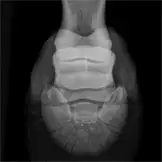

Die Anwendungsbereiche für röntgenologische Untersuchungen sind sehr vielfältig. Fast jede Lahmheitsuntersuchung und orthopädische Untersuchung erfordert die röntgenologische Darstellung bestimmter Gliedmassenabschnitte in mehreren Ebenen. Nahezu jede Kaufuntersuchung beinhaltet neben der klinischen Untersuchung auch die Erstellung von Röntgenbildern der Gliedmaßen und in vielen Fällen auch der Oberlinie. Bei bestehenden Rittigkeitsbeschwerden wird häufig eine Röntgenuntersuchung des Halses und des Rückens vorgenommen. Aufgrund der Leistungsstärke unserer Röntgenanlagen ist es uns häufig möglich, auch den Beckenbereich des Pferdes inklusive Hüftgelenk am stehenden Pferd zu untersuchen.